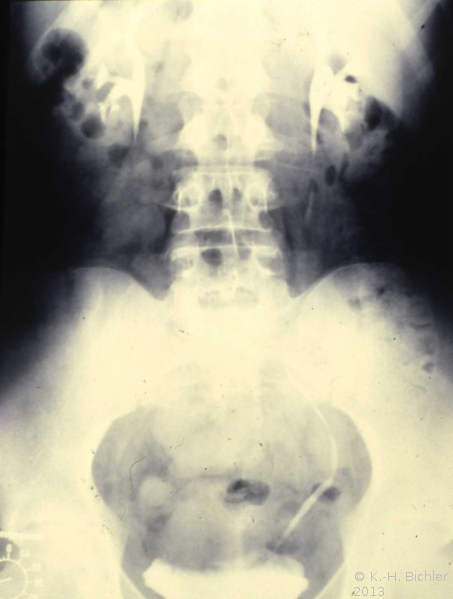

Die Röntgenübersicht der Niere und ableitenden Harnwege zeigten keinen Anhalt für Konkrement. Im Ausscheidungsurogramm eine "stumme Niere" links (Abbildung 19a). Bei der retrograden Sondierung links fand sich keine Abflussbehinderung (Stein oder Stenose) (Abbildung 19c). Im MCU kein Anhalt für Reflux (Abbildung 19b). Im Nierenfunktionsszintigramm MAG3 wurde eine seitengetrennte Funktionsverteilung von rechts zu links wie 93% zu 7% festgestellt. Zur Abklärung eventueller Gefäßalterationen erfolgte eine Renovasographie mit dem Nachweis einer langstreckigen Stenose der linken Arteria renalis (Abbildung 19d). Wegen des Verdachtes auf eine generalisierte Arteriitis wurden Angiographien weiterer Gefäßgebiete durchgeführt: Dabei fanden sich eine geringgradige Einengung der infrarenalen Aorta und der linken Arteria subclavia.